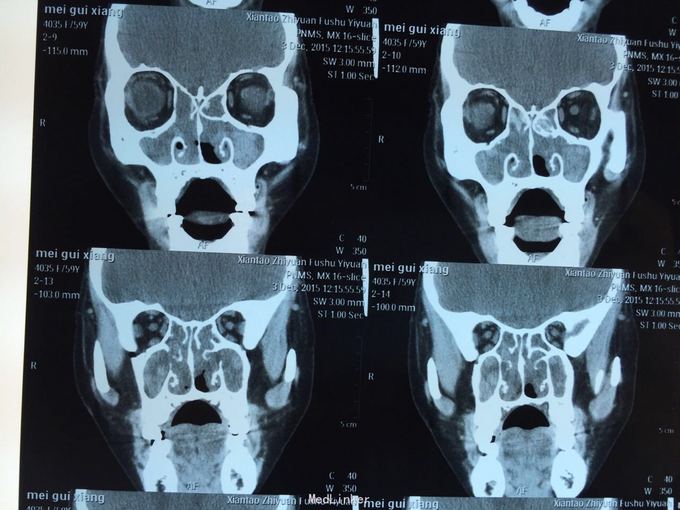

患者鼻塞分泌物增多,一年余,自诉曾于03年及09年两次鼻息肉摘除手术,现查鼻内镜双侧鼻腔可见大量息肉样物,鼻窦ct示全组鼻窦炎,鼻腔息肉。患者拟住院行第三次鼻息肉手术。